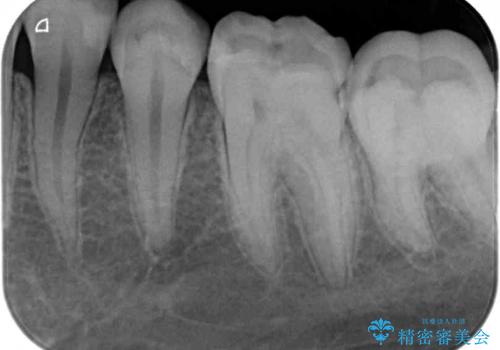

- 以前治療した詰め物が欠けてしまったことを主訴として来院した患者様です。

食べ物がはさまったり、冷たいものがしみるといった症状がみられました。

むし歯の染め出し液と拡大鏡を用いて、むし歯がないことを確認し、

セラミックインレーにて修復することとしました。

食べ物がはさまりにくくなり、冷たいものがしみる症状もなくなり、大変満足していただきました。